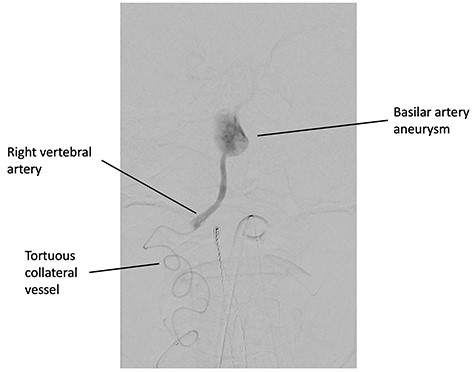

A 60-year-old male initially presented for investigation of headaches and underwent a contrast enhanced computed tomography scan of his brain. The scan revealed a 20 mm × 10 mm basilar artery aneurysm that was deemed not surgically operable (Fig. 1). Such an aneurysm carries an 18.4% 5-year rupture risk [4]. His past medical history included coronary artery disease, atrial fibrillation, a metallic mitral valve, a prior ischaemic stroke, hypertension and a previous provoked deep vein thrombosis. He was otherwise a functionally independent, relatively young man with an incidental but high-risk aneurysm that required treatment. Anatomically, his left vertebral artery terminated in the posterior inferior cerebellar artery (PICA) and did not communicate with the aneurysm. The right vertebral artery was occluded at its origin and reconstituted via collaterals from the right thyrocervical trunk at the V3 segment. Attributable to significant tortuosity of this vessel, the initial attempt at stenting the aneurysm was unsuccessful.

Digital subtraction angiography, demonstrating the catheter in the tortuous collateral vessel from the right thyrocervical artery supplying the right vertebral artery.